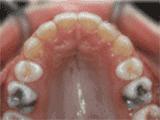

3、牙齿拥挤,个别牙异位,牙弓狭窄,导致局部牙齿重叠生长,两侧各拔牙一颗后,经过矫正是变成这样的~